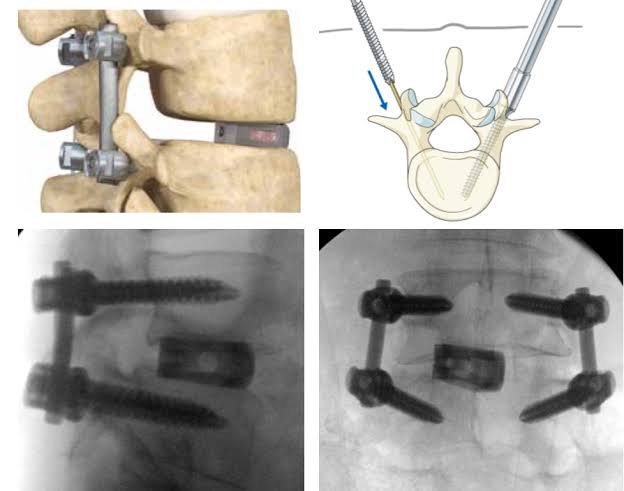

How is MIS TLIF Performed?

- Surgery is done under general anesthesia

- A small skin incision (2–3 cm) is made

- Tubular retractors gently separate muscles (no cutting)

- Nerve compression is relieved

- The damaged disc is removed

- Bone graft and cage are placed between vertebrae

- Pedicle screws and rods stabilize the spine

- Incision is closed with minimal tissue trauma